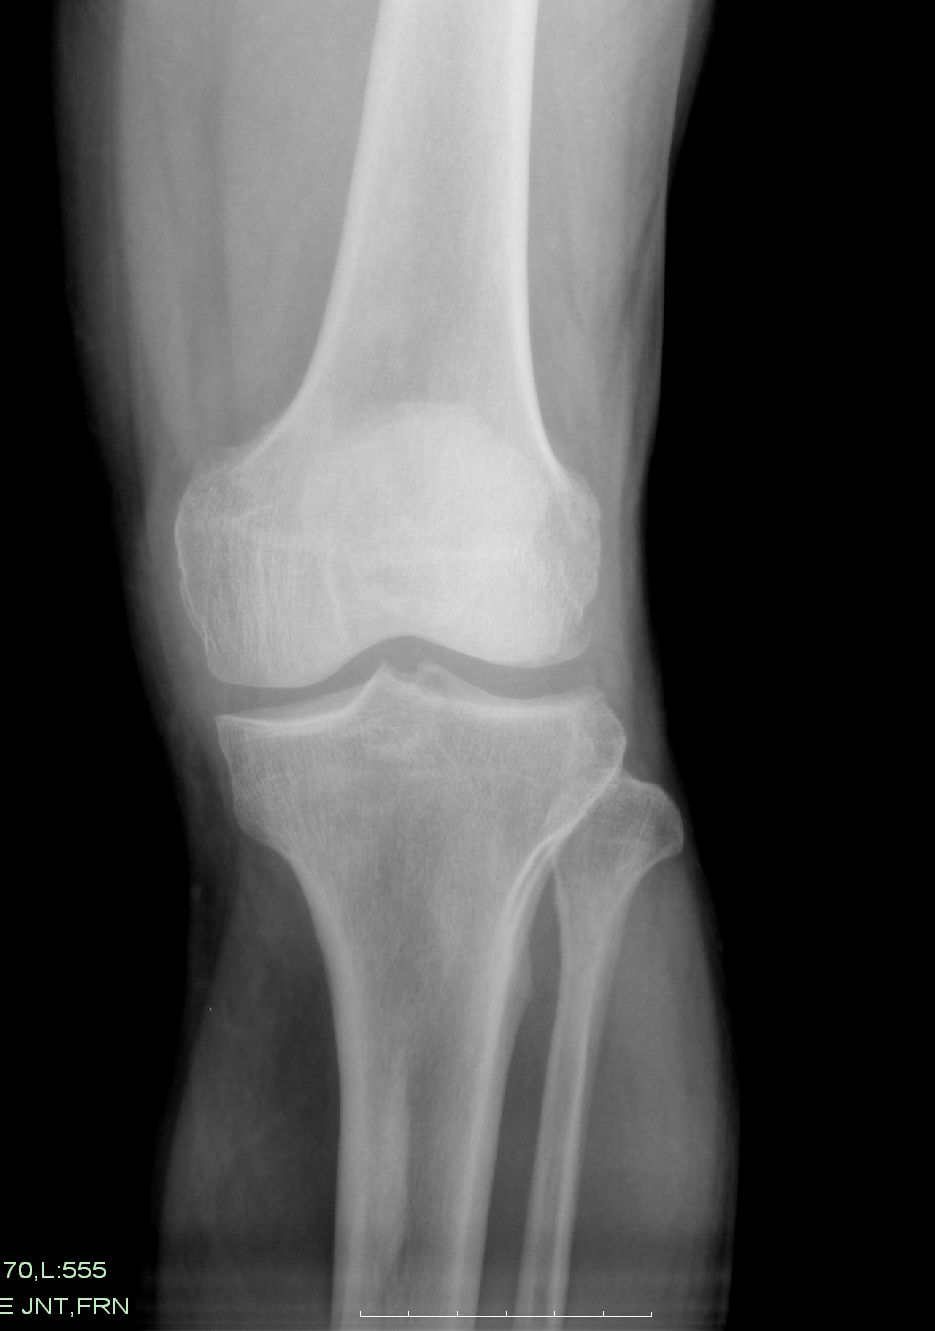

以下是引用zxl51642在2009-9-4 10:43:00的发言:[br]1、关节退变,2、局限性骨皮质增厚,无意义,长期观察,必要时mri。

以下是引用zjzjr在2009-9-4 16:06:00的发言:[br]局限性骨皮质增厚,轻度退行性变

以下是引用黑白光影在2009-9-4 14:38:00的发言:[br]膝关节构成骨有轻度退行性改变,胫骨上段前内侧局限性骨皮质增厚,正如6楼所说。